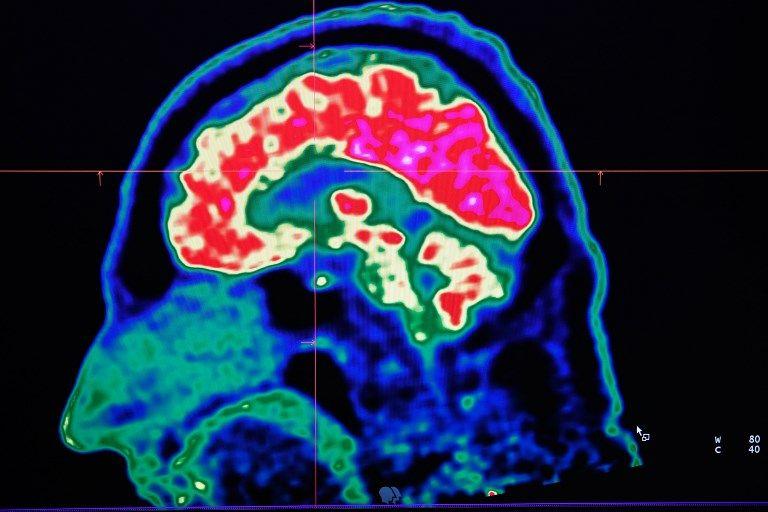

Le cerveau, principe de la puissance de l’homme et ruine de son avenir ?

Sébastien Bohler vient de publier "Le bug humain, Pourquoi notre cerveau nous pousse à détruire la planète et comment l’en empêcher" (Robert Laffont). Il apporte un éclairage nouveau et original sur la question du devenir contemporain. Le premier coupable à incriminer n'est pas l'avidité des hommes mais bien la constitution même de notre cerveau. Extrait 1/2.